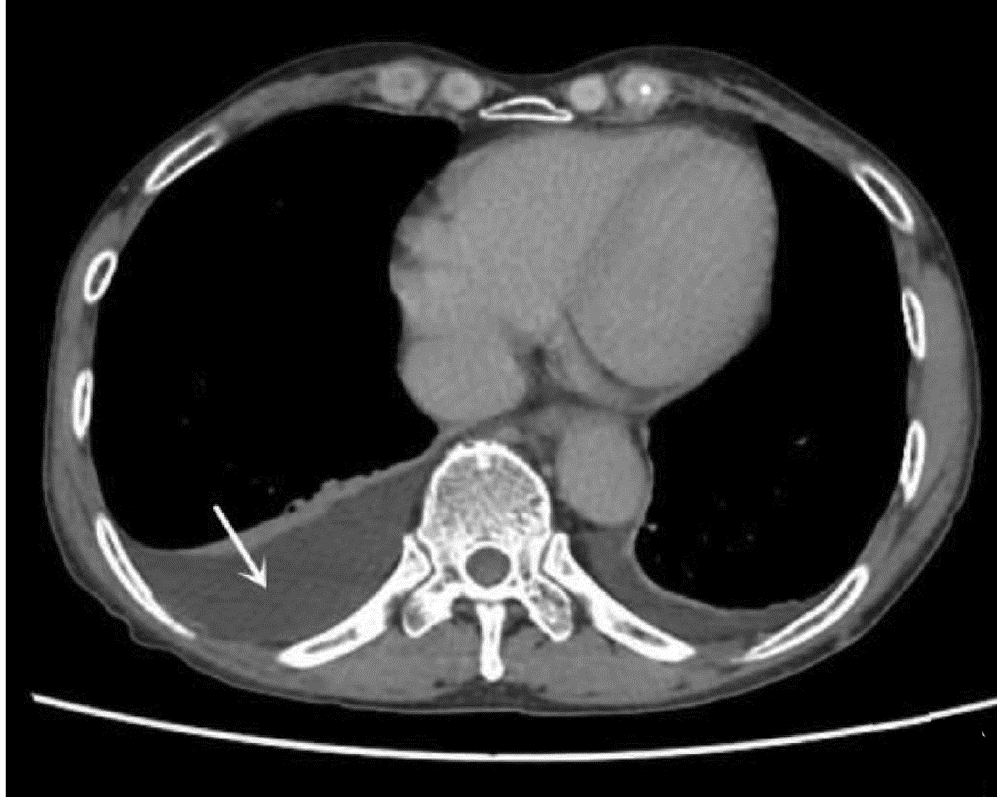

ZOU YX. Parasitic infections involving the pleura[J]. Chin J Pract Pediatr, 2017, 32(3): 181-186. DOI: 10.19538/j.ek2017030607.

邹映雪. 寄生虫性胸腔积液[J]. 中国实用儿科杂志, 2017, 32(3): 181-186. DOI: 10.19538/j.ek2017030607.

WEI CZ, HUANG LY, ZENG YH, et al. Liver fluke pleural effusion in 4 cases and literature review[J]. Clin Focus, 2009, 24(20): 1825-1827. https://www.cnki.com.cn/Article/CJFDTOTAL-LCFC200920048.htm

韦彩周, 黄陆颖, 曾莹晖, 等. 肝吸虫相关胸腔积液4例并文献复习[J]. 临床荟萃, 2009, 24(20): 1825-1827. https://www.cnki.com.cn/Article/CJFDTOTAL-LCFC200920048.htm